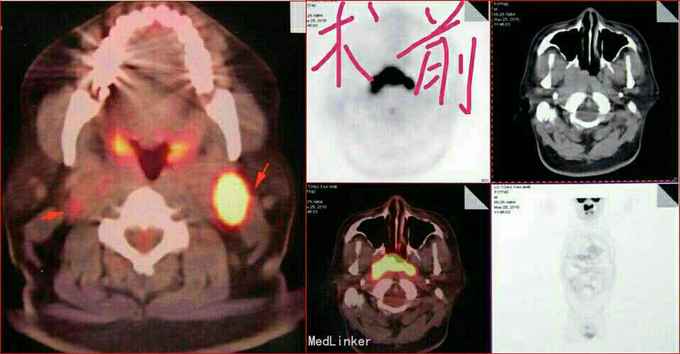

男性,46岁,鼻咽部鳞癌放疗后复发,因回吸性涕血、鼻塞、耳鸣、头痛入院。 2010.05.25行PET—CT示:鼻咽部不规则高代谢肿物,颈部淋巴结肿大。

查体:生命指征平稳,一般状况可;2010.05.25行PET—CT示:鼻咽部不规则高代谢肿物,颈部淋巴结肿大。